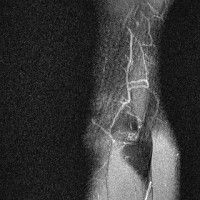

무릎 mri 간단히 봐주실 수 있으시나요 ㅠㅠ

안녕하세요 8년전 십자인대 수술하고 최근 무리한 운동에 무릎 불편감이 생겨서

mri 찍었습니다.

진단결과는 첫 찍은 병원에서 활액막염 이라는 진단을 받았습니다. 혹시 봐주실 수 있으실까요?

진단결과가 달라 혼란스럽습니다 ㅠㅠ

• 안녕하세요. 강성주 의사입니다.

올라온 MRI가 단편적이라서 정확한 진단에 어려움이 있지만 십자인대에는 큰 이상이 있지는 않은것 같으며, 무릎관절내 물이 있는 것으로 보아 활액막염의 진단이 맞을 것 같습니다.

하지만 단편적인 영상이기 때문에 촬영병원에서 정확한 판독지 등을 받으시는 것이 좋겠습니다.